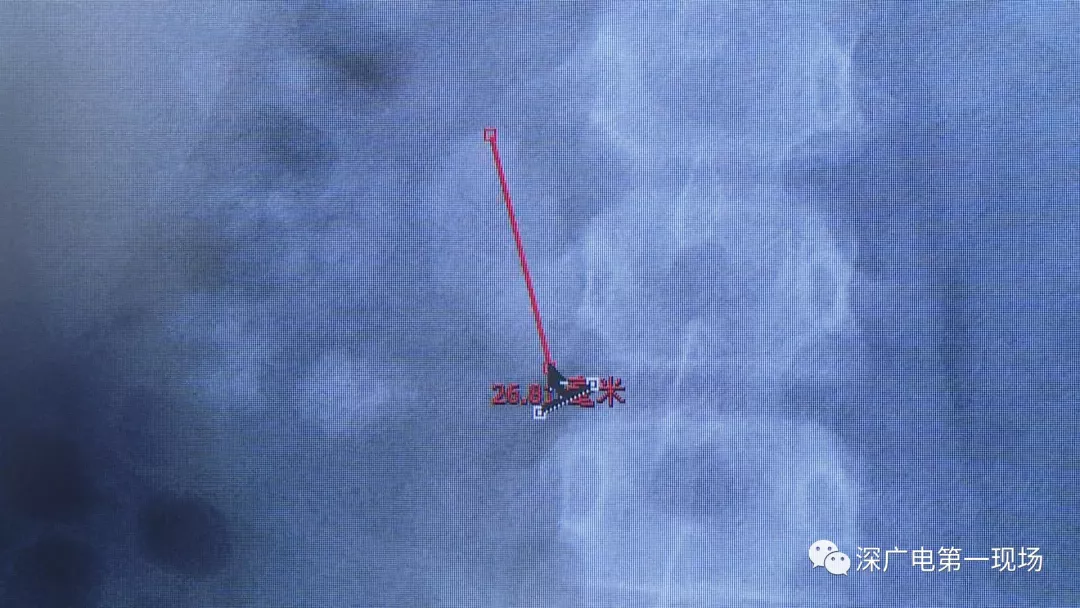

在X光圖像下,醫(yī)生發(fā)現(xiàn)小軒的雙側(cè)腎臟都內(nèi)藏乾坤,密密麻麻的分布著大小不等的結(jié)石。

醫(yī)生這么解釋:通常情況下,成人只要有0.5厘米大小的結(jié)石造成尿路梗阻,就需要及時(shí)治療。

小軒這種情況,其中,最大的結(jié)石長(zhǎng)約2.7厘米,寬約1.7厘米,體積堪比鵪鶉蛋,不但造成了尿路堵塞,還導(dǎo)致了右腎中度積水。